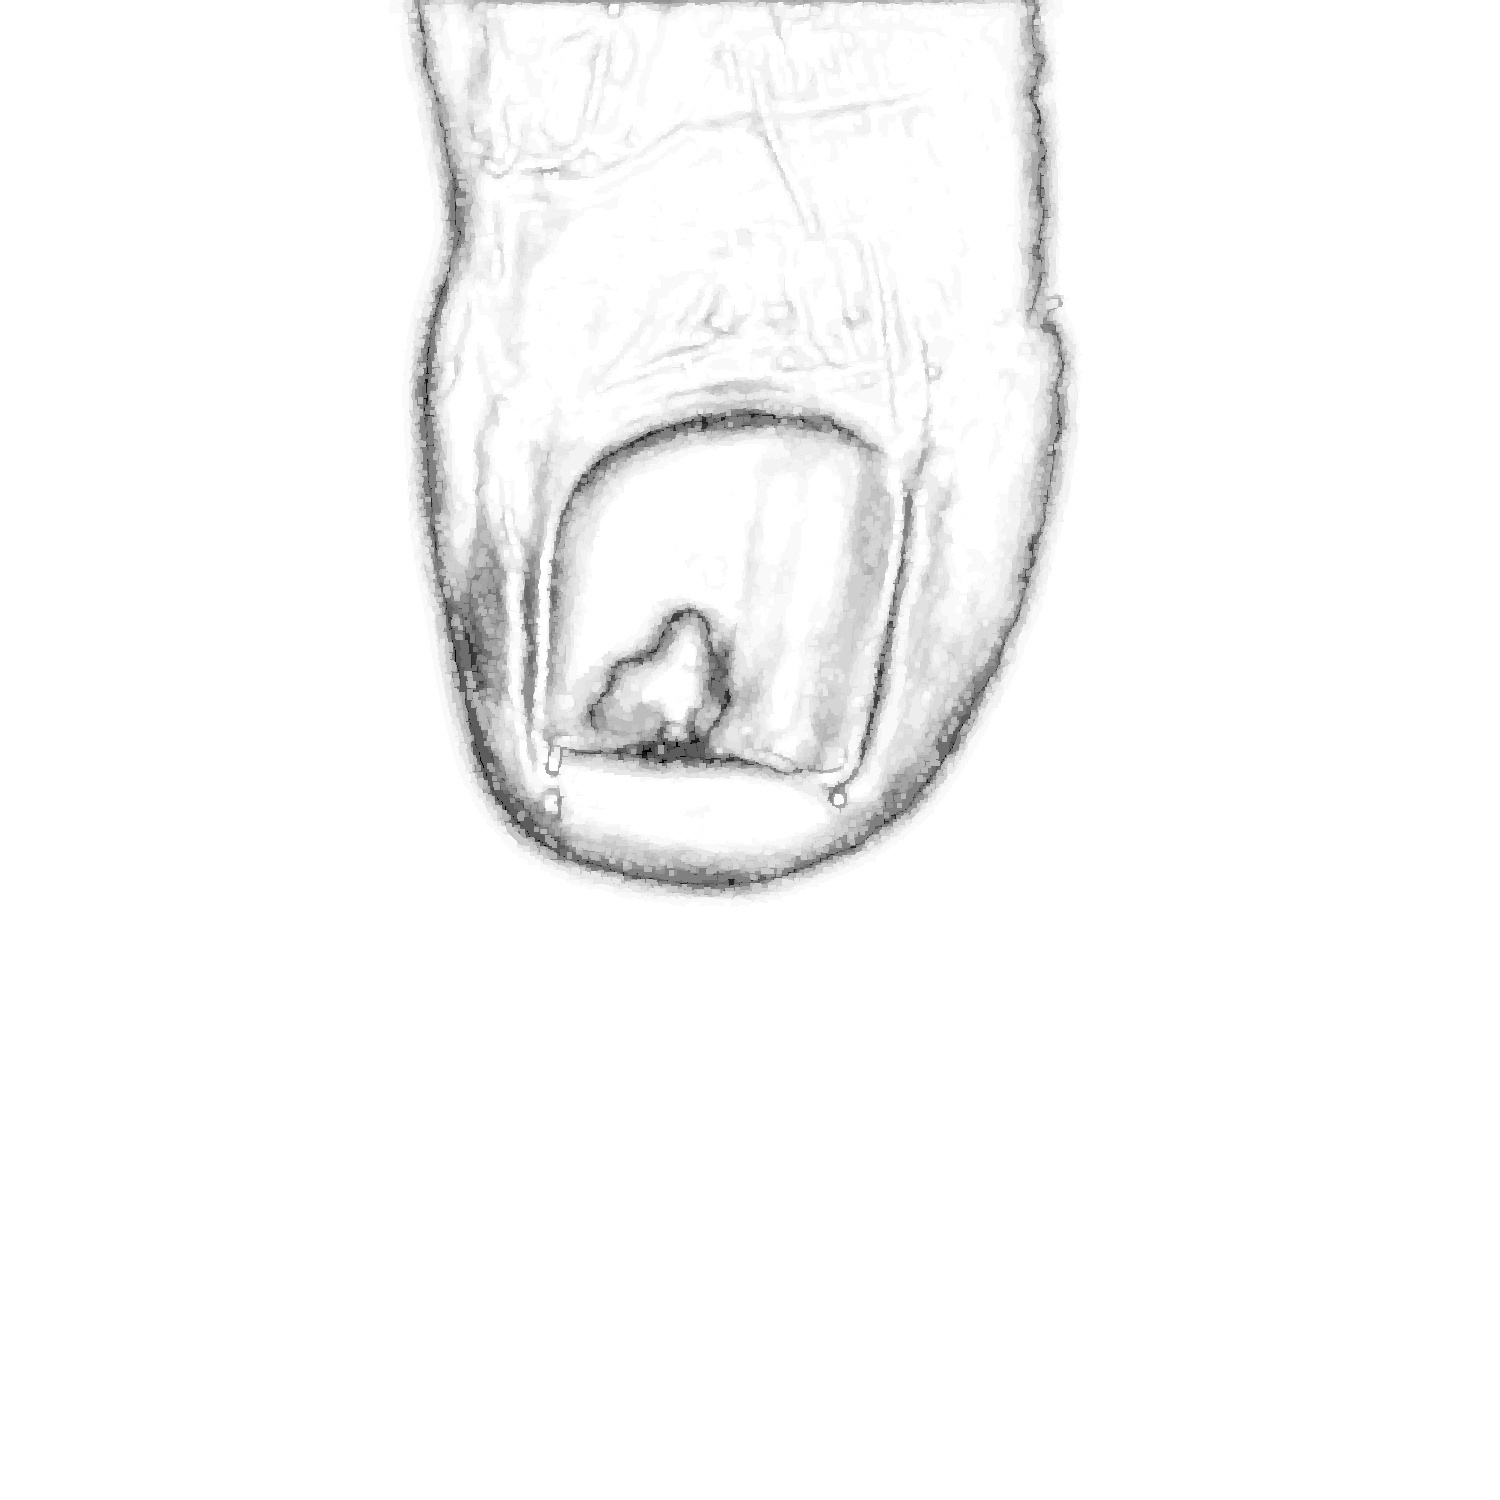

Before tackling the image segmentation problem, we perform an image normalization process based on the template’s known measures. It consists on transforming the input image, as seen in Fig. 3 (left), to an image with standard dimensions and orientation, Fig. 3 (right). To achieve our objective we detect the position of the template corners and geometrically transform the image with an affine mapping. As a result, all normalized images appear to had been taken under the same point of view. We remark that the three template colored squares are mapped to the top-right, bottom-right and bottom-left image corners. In particular, left foot images are mirrored. Normalized images are always set to measure pixels. Since the real region inside the template measures cm, a centimetre in the normalized image accounts for 300 pixels, which can be used to measure distances and areas.

In the following, we describe each step taken to deal with the task of segmenting the toenail from images like the one in Fig. 3 (right). In particular, Fig. 4 contains a flow diagram, along with the algorithm employed for each of them.